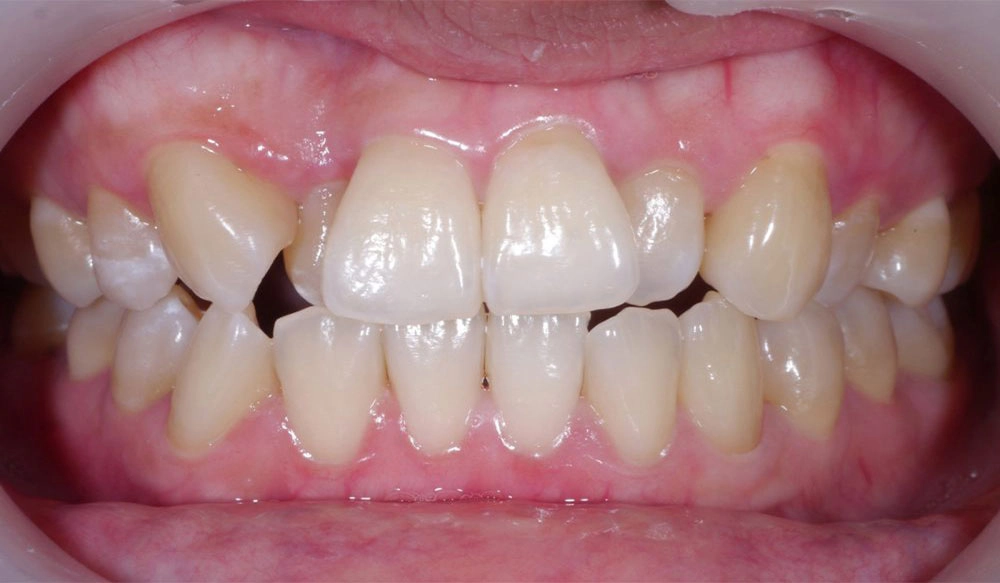

Class II

Class II — or "overbite" — is the condition in which the mesiobuccal cusp of the upper first molar is positioned mesially to the mesiobuccal groove of the lower first molar instead of both being aligned, affecting the occlusal relationship between both dental arches.

Patient Information:

Age: 24

Gender: Female

Invisalign Treatment Option: Invisalign Comprehensive

Total Treatment Time:

21 Months